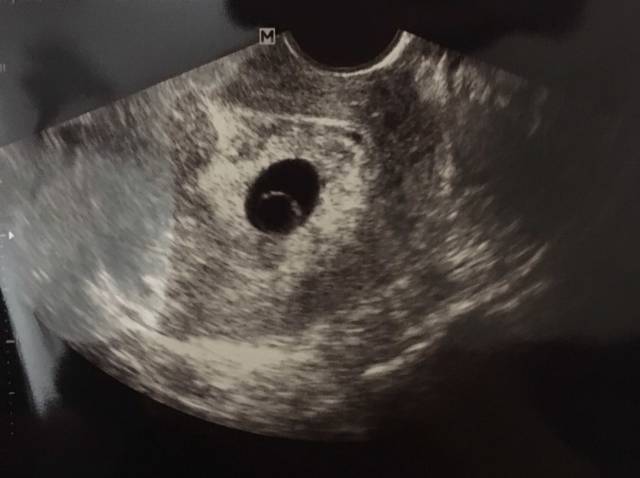

什么是卵黄囊

什么是卵黄囊,卵黄囊是什么意思

图文并茂:你所不了解的卵黄囊

卵黄囊b超图

卵黄囊图片长什么样

卵黄囊图片

b超下的卵黄囊图

正常的卵黄囊图片